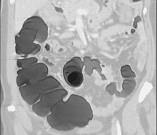

问题 女,56岁,腹胀、腹痛、左下腹包块三月余,无肛门排气,影像检查如图,最可能的诊断是()

选项 A.乙状结肠Crohn病 B.乙状结肠结核 C.乙状结肠腺癌 D.乙状结肠淋巴瘤 E.乙状结肠息肉

答案 C